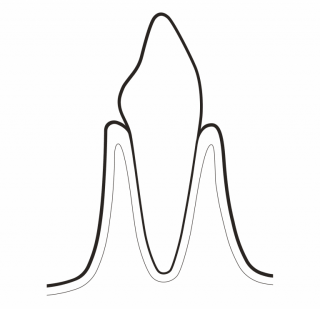

05 PERIOFLOW®

Remove biofilm in >4 to 9 mm pockets:

- Use PLUS Powder on natural teeth in deep pockets and root furcations and on implants

- Use new and slimmer PERIOFLOW® Nozzle

TREAT PERIODONTITIS

PERIOFLOW® with PLUS Powder preserves cementum during periodontal maintenance. It effectively removes subgingival biofilm in residual deep pockets. The PIEZON® PS NO PAIN Instrument removes the remaining calculus in a minimally invasive way. Final check ensures that no calculus remains.